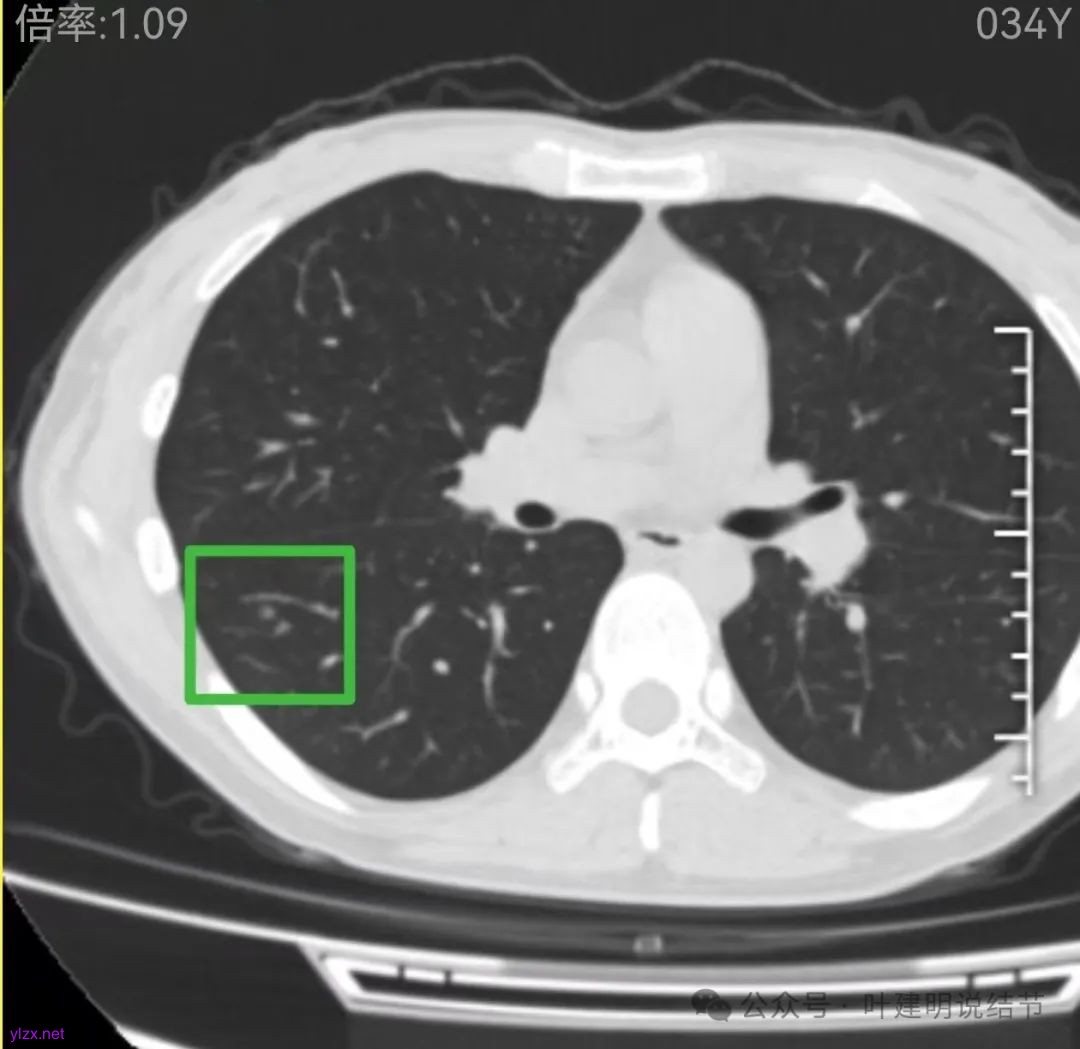

再看2022年9月的影像:

右下当时是很淡的,也显偏模糊的磨玻璃影。

怎么有个点状密度较高的结节在?与上面那截图的淡磨并不完全在一块的。

密度甚高,边界与轮廓清楚,只看这真的不像恶性些。

边缘区也瘤肺界限稍糊,整体轮廓还行。有进展的是不是就是淡磨那处?

两肺多发结节,左侧黄色标注的考虑是肺泡上皮增生可能性大;蓝色的考虑肺泡上皮增生或者少许慢性炎可能性大;右侧红色宽起来并带有红色箭头的这处是主病灶,偏混合密度,整体轮廓较为清楚,边缘显得毛糙,从2024年12月份的来看,要考虑是肿瘤范畴,原位癌或者微浸润性腺癌可能性较大,也不能完全排除不典型增生。但是在2022年的时候,这个病灶的边上也有一个实性的微小结节,如果只看2022年的,这么小的实性结节,又比较圆,表面也显得较为光滑,是要考虑良性的,当然太小了需要动态观察。回头再重新来看2024年底的,发现绿色箭头所指的这个微小实性的较2022年几乎没有变,去仔细寻找2022年的,发现当时在实性结节旁边也有密度很淡的一点磨玻璃影(也可能真的就是一处,只是扫描不够薄,密度的变化有些突兀而已),而到了2024年12月份,实性微小这处没有明显变化,但是原来很淡的磨玻璃变成了混合磨玻璃,范围也明显扩大。所以总体来看右肺下叶这处是考虑恶性的,而且从磨玻璃结节角度来讲,还是生长比较快的,就是说还是有一定风险的。加上左侧还有两处也是磨玻璃持续存在,虽然边缘轮廓显模糊一点,但多年以后也可能仍然要变成原位癌或者微浸润性腺癌之类的东西。通盘考虑以后,我倾向于右侧近期单孔胸腔镜下微创局部切除,左侧随访观察,等到有进展并风险增加再来考虑处理。意见供参考!